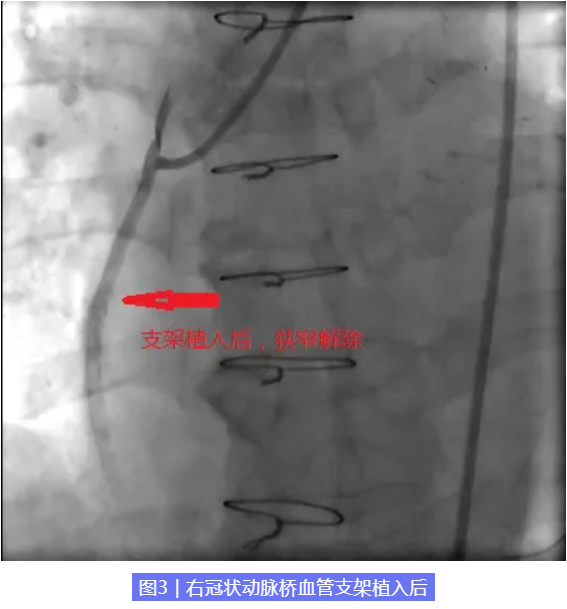

经我院特聘专家北京阜外医院张海涛主任、北京燕化医院心内科李钢主任和王志勇副主任医师全面、综合评估患者病情及血管情况,考虑患者靶病变为桥血管,建议优先解决桥血管病变。经医院心内科介入团队审慎讨论并征得患者同意后,考虑到患者桥血管内存在大量血栓,极易出现无复流现象,决定对患者右冠桥血管行准分子激光销蚀术。一个多小时后,我们成功在患者右冠桥血管狭窄处植入一枚支架,术后患者胸痛症状缓解。